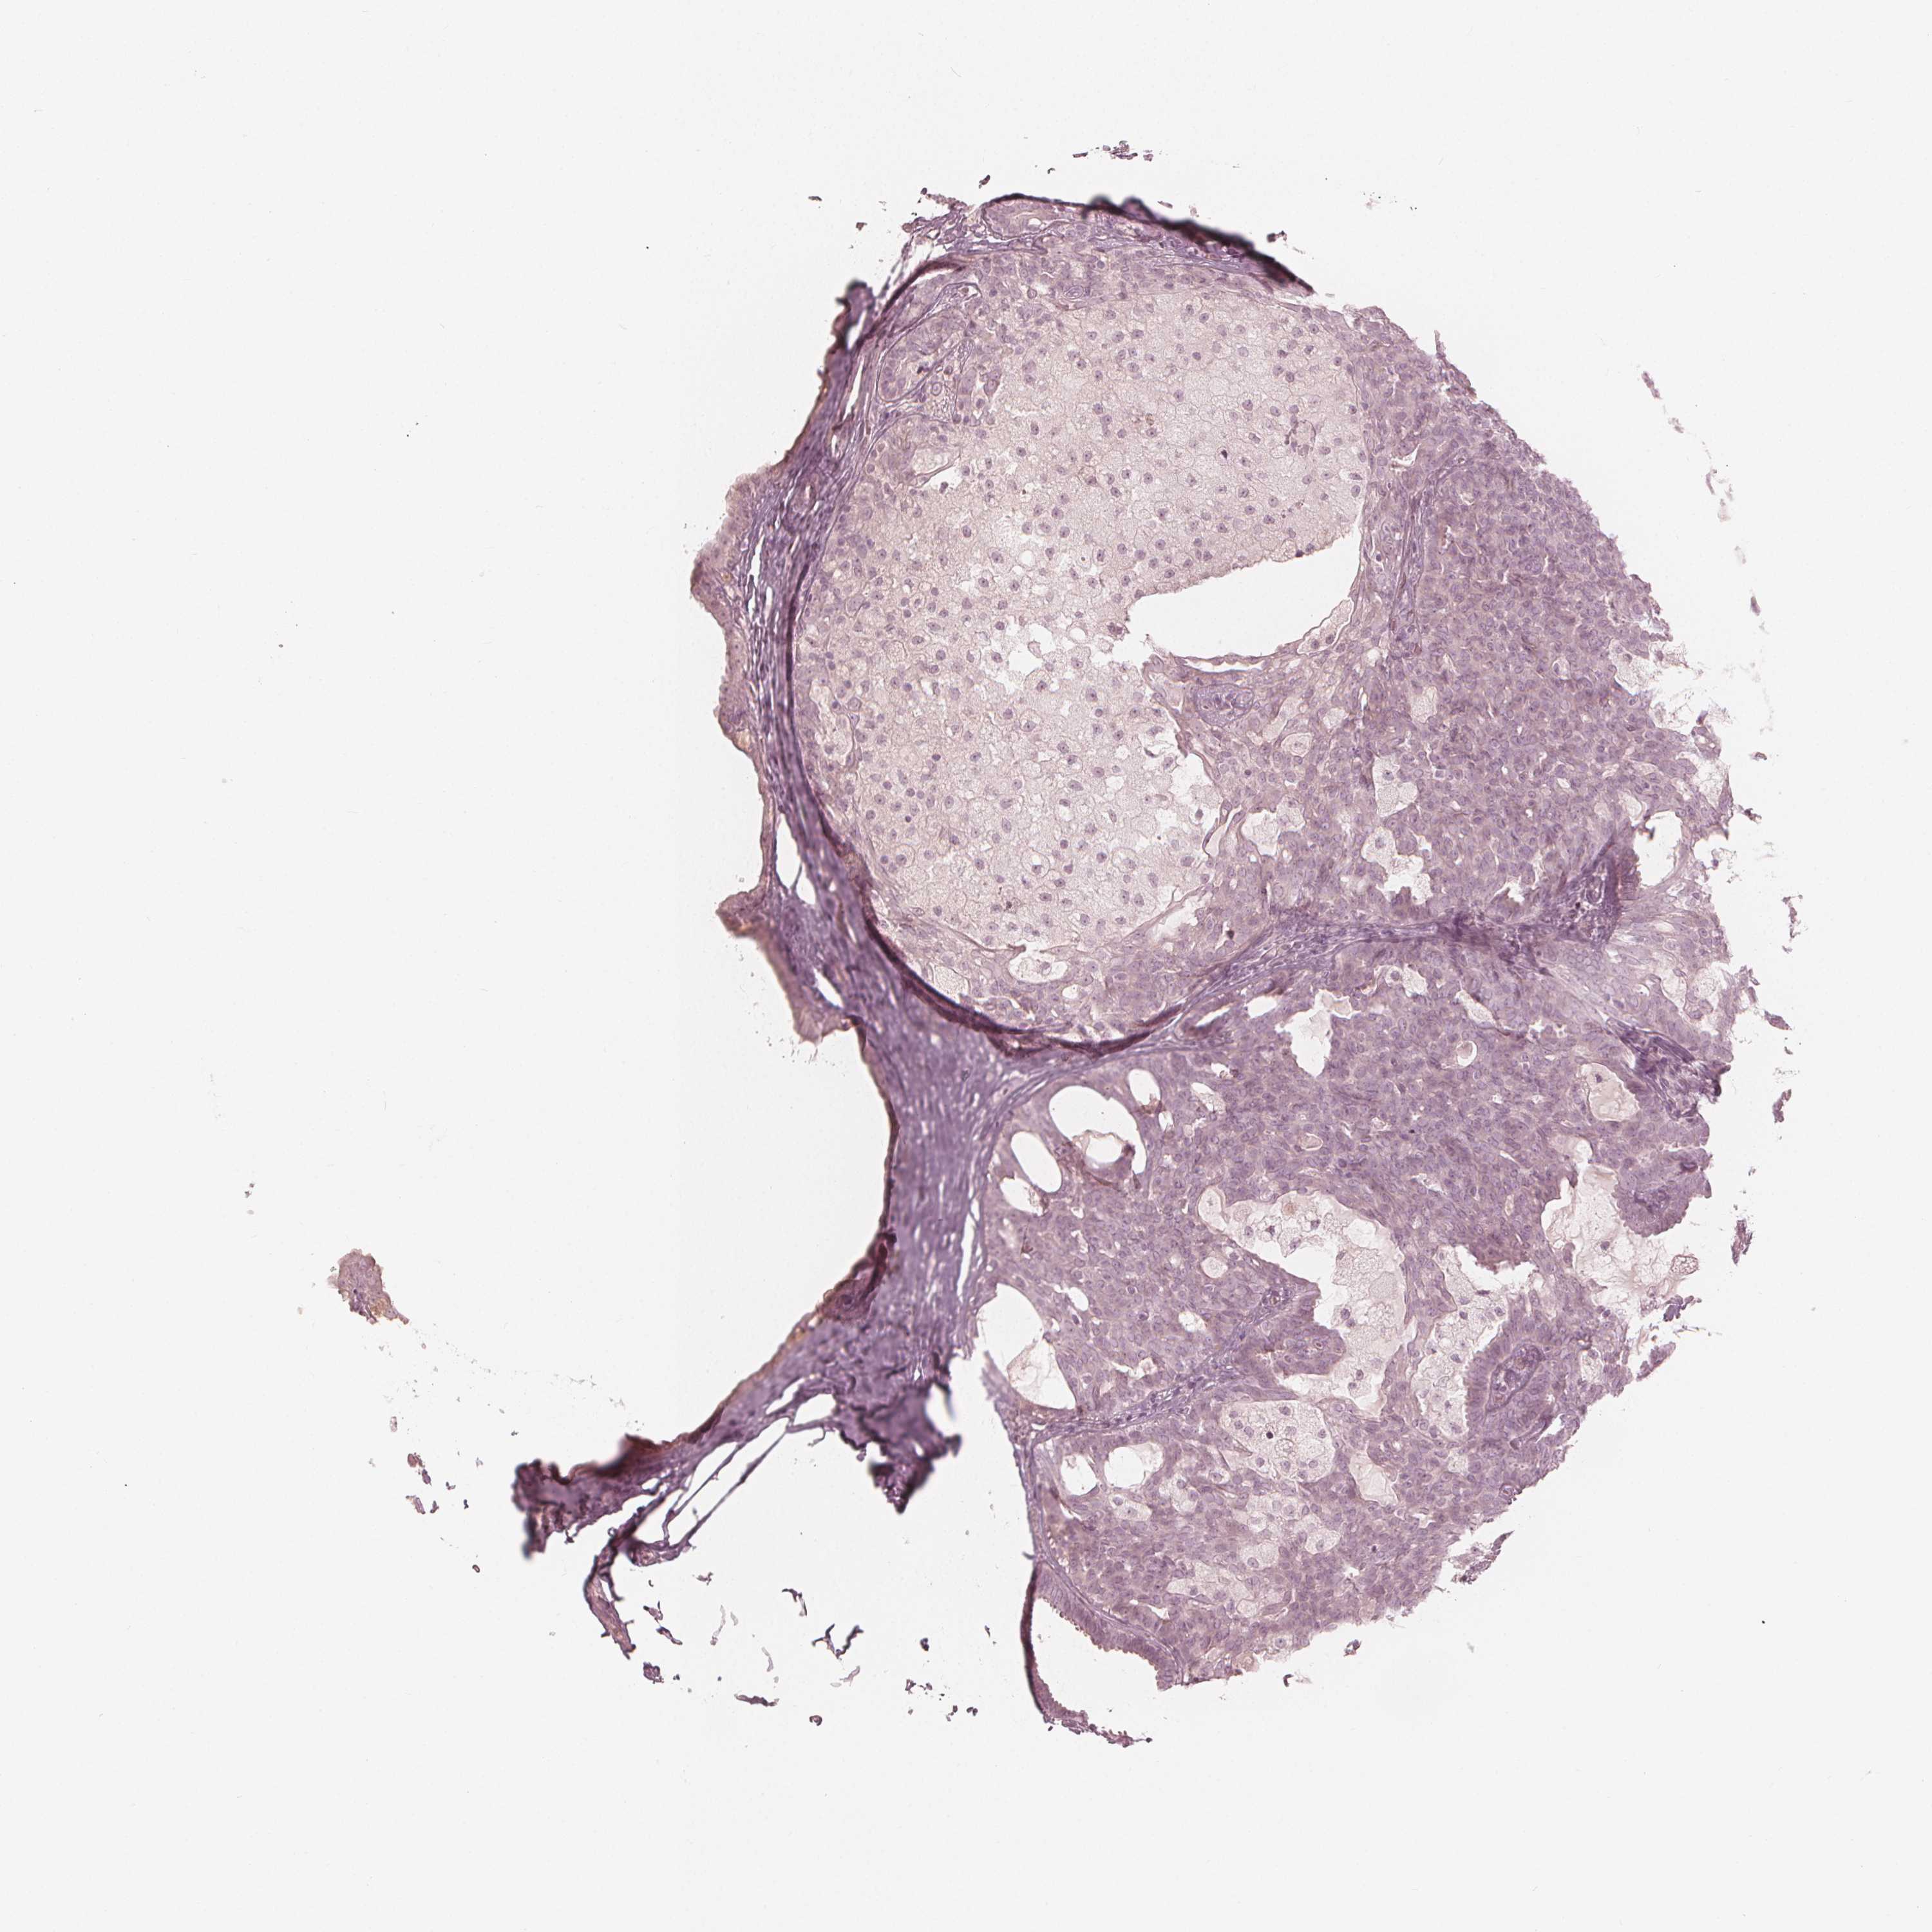

CANCER BREAST CANCER Show tissue menu

BRCA TCGA BRCA VALIDATION PROTEIN EXPRESSION